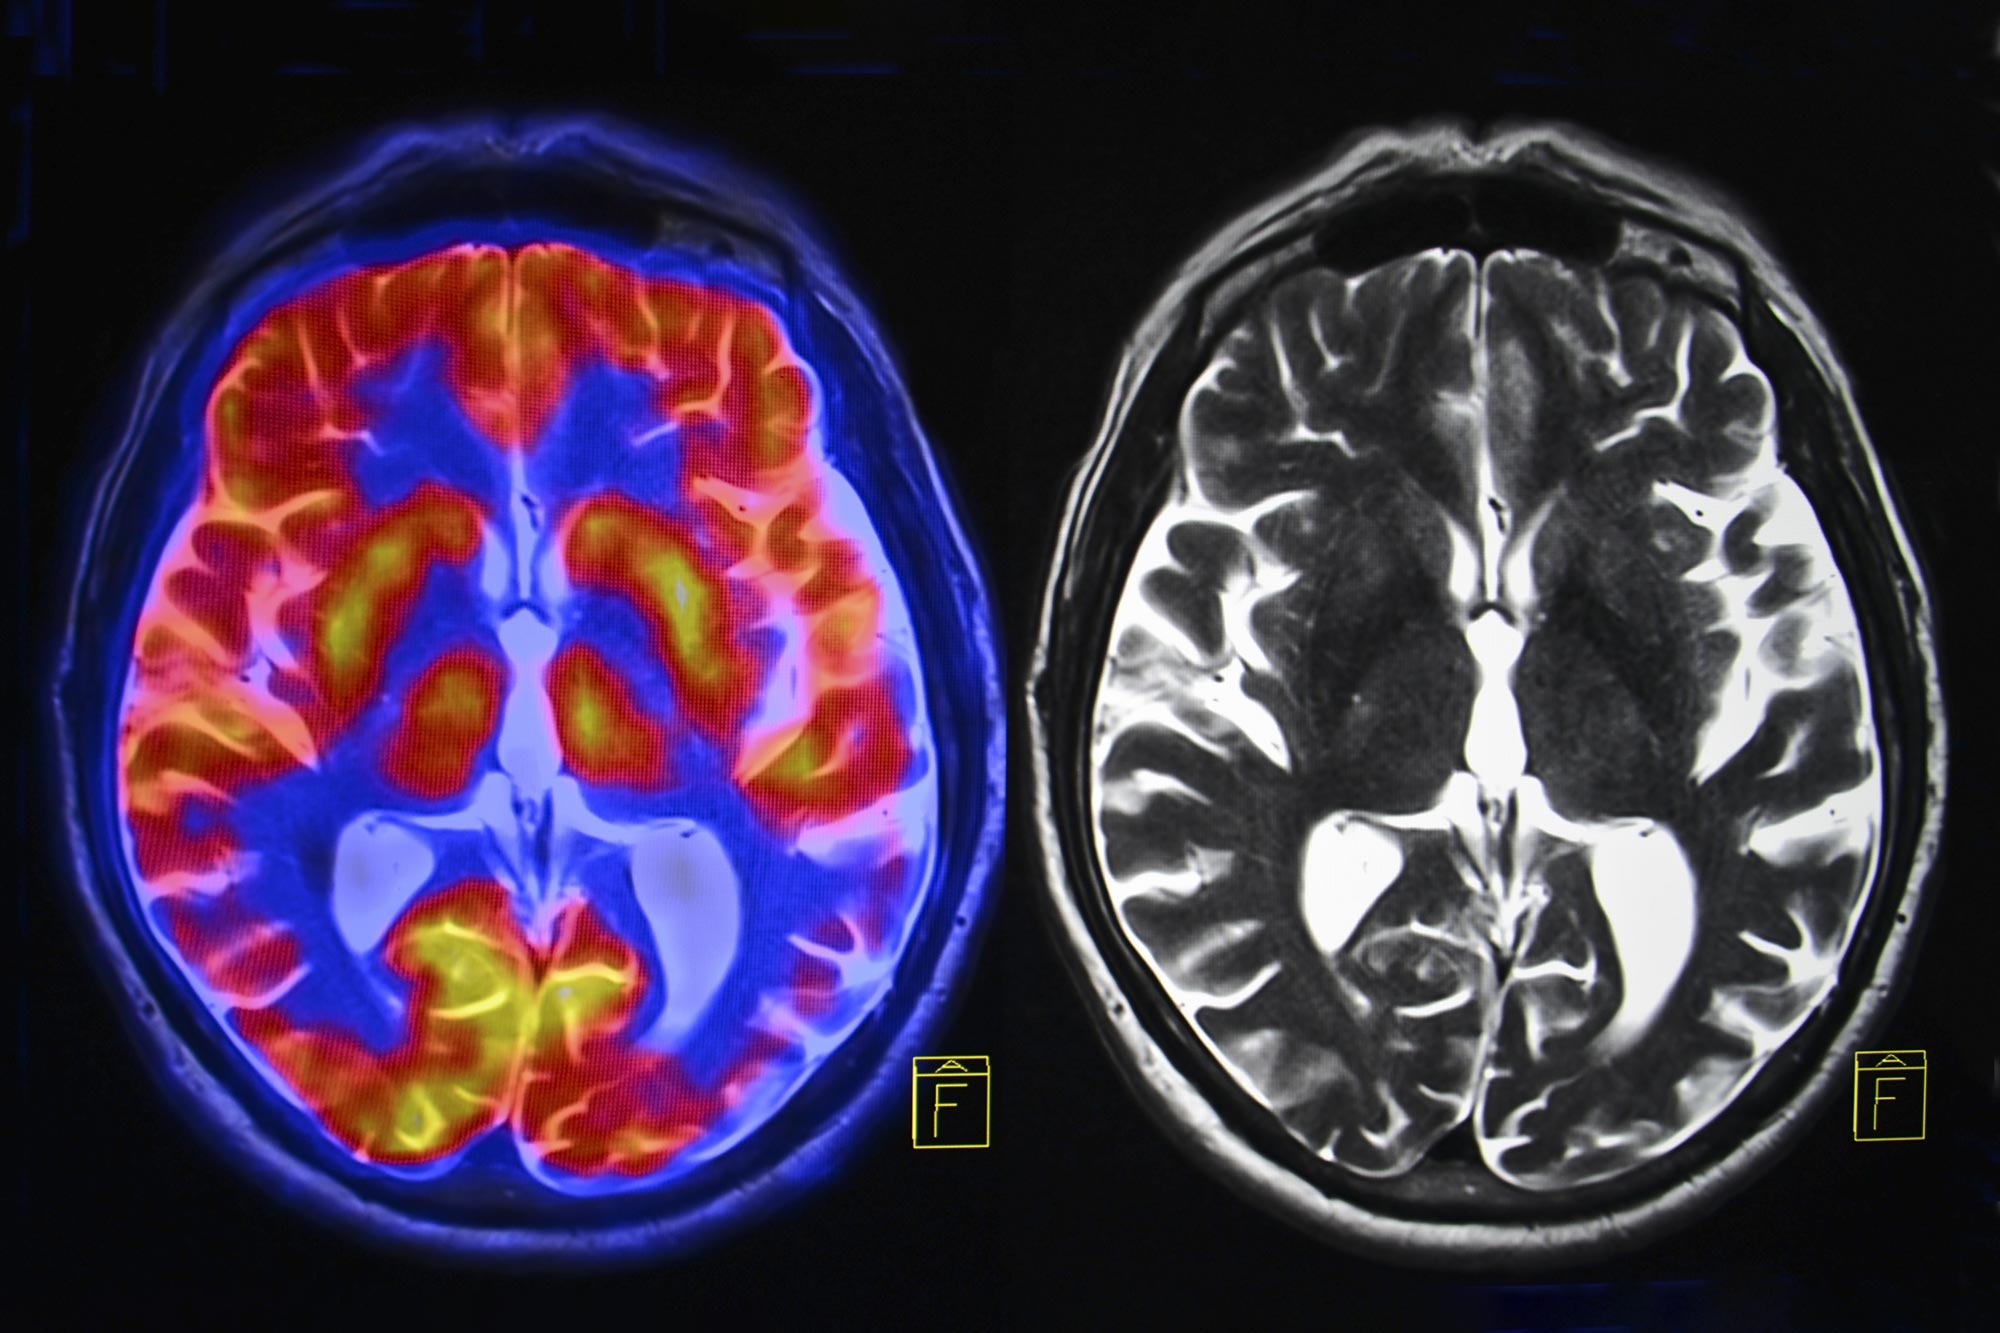

To explore this idea, Liu’s team analyzed multiple types of brain imaging data from more than 800 participants in the United States and China. The study included people with Parkinson’s disease receiving DBS or non-invasive therapies such as transcranial magnetic stimulation, focused ultrasound stimulation, and medications. Healthy volunteers and individuals with other movement disorders were also included for comparison.

The researchers found that Parkinson’s disease is marked by unusually strong connections between the SCAN and the subcortex, a brain region involved in emotion, memory, and motor control. Across all four treatments examined in the study, the therapies worked best when they reduced this excessive connectivity. Doing so helped restore more normal activity in the brain circuit responsible for planning and coordinating actions.

“For decades, Parkinson’s has been primarily associated with motor deficits and the basal ganglia,” the part of the brain that controls muscle movements, Liu said. “Our work shows that the disease is rooted in a much broader network dysfunction. The SCAN is hyperconnected to key regions associated with Parkinson’s disease, and this abnormal wiring disrupts not only movement but also related cognitive and bodily functions.”